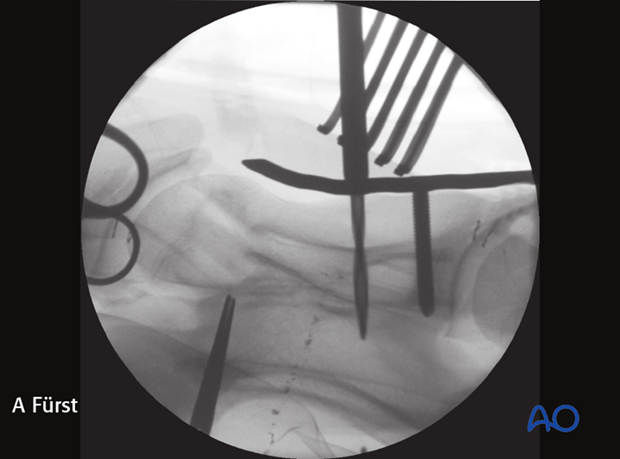

Intraoperative radiographic control of the drilling depth and screw positioning is critical to prevent penetration of the vertebral canal.

The image shows intraoperative radiographic control of the drilling depth and screw positioning.

Note: Penetration of the spinal canal with the drill must be avoided.

Intraoperative image showing penetration of the spinal canal.